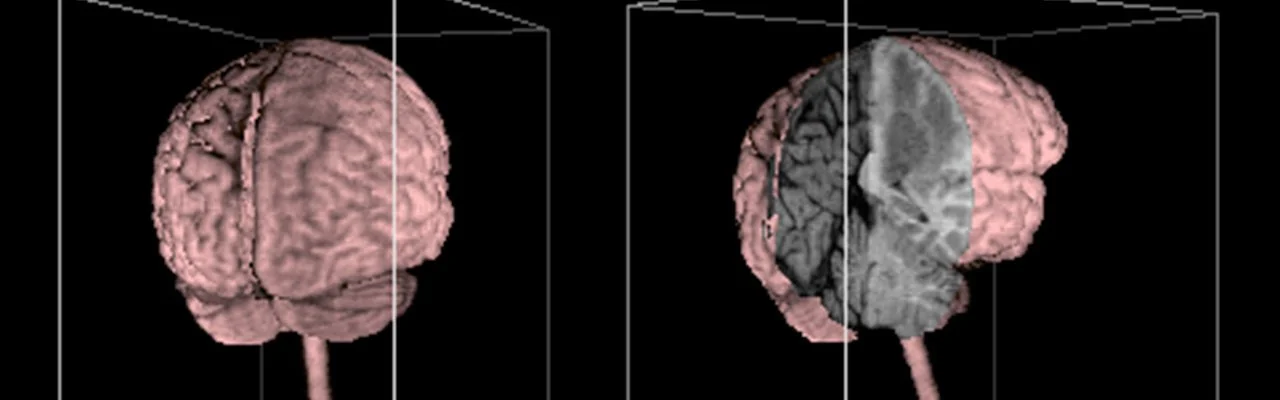

Advances in rendering technology, cloud computing, and data processing are enabling medical imaging datasets to be reconstructed into fully interactive 3D models. Instead of passively scrolling through slices, clinicians can now explore anatomy as volumetric structures in space.

Interactive 3D visualization allows users to rotate, zoom, isolate, and examine anatomical regions from any angle. This transforms imaging from a static review process into an exploratory experience that more closely reflects how anatomy exists in the real world.

Rather than imagining how structures relate to each other, clinicians can directly observe those relationships, leading to faster comprehension and more confident clinical decisions.

3D image of brain